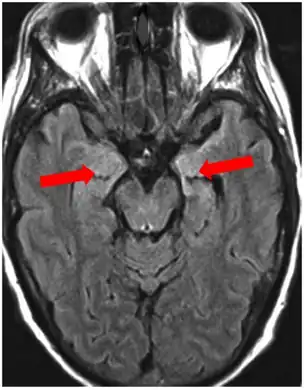

Brain MRI is the mainstay of initial investigation pointing to limbic lobe pathology revealing increased T2 signal involving one or both temporal lobes in most cases.[22][14]

Serial MRI in LE starts as an acute disease with uni- or bilateral swollen temporomesial structures that are hyperintense on fluid attenuation inversion recovery and T2-weighted sequences. Swelling and hyperintensity may persist over months to years, but in most cases progressive temporomesial atrophy develops.[23]